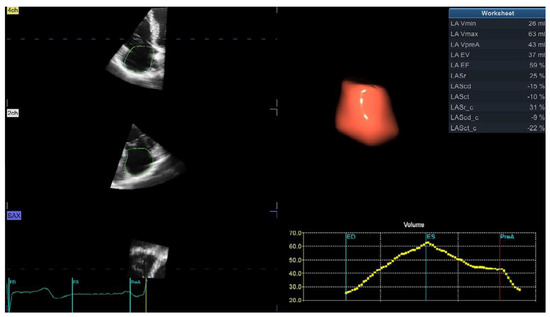

The right atrium (RA) is enlarged in hypertensive patients, and our study showed that the phasic function is significantly influenced by systemic BP [21]. RA phasic function gradually deteriorated from patients with optimal BP, across patients with high-normal BP, to those with arterial hypertension [21]. A study that investigated the influence of different LV geometric patterns reported that RA conduit and reservoir function gradually decreased and RA pump function gradually increased from hypertensive patients with normal LV geometry to those with LV dilatation and concentric LVH [31]. RA dilatation and dysfunction significantly contribute to RV diastolic dysfunction in hypertensive patients and may explain changes in RV filling pressures assessed by tricuspid E/A and E/e’. Nevertheless, RA enlargement was not proven to be an independent predictor of adverse events in hypertensive patients [5]. New 3D echocardiographic software provides a rapid and simultaneous evaluation of RA volumes and volume-derived phasic function (Figure 2).

Figure 2.

Three-dimensional echocardiographic volume- and strain-derived right atrial phasic analysis (software is dedicated for left atrial analysis and, therefore, all acronyms are devoted to the left atrium (LA) and should be replaced with the right atrium (RA) as the same software is used off-label for the RA). ED—end-diastole, ES—end-systole, LA EV—left atrial emptying volume, LA EF—left atrial emptying fraction, LASr—left atrial longitudinal strain during reservoir phase, LAScd—left atrial longitudinal strain during conduit phase, LASct—left atrial longitudinal strain during contraction phase, LASr_c—left atrial circumferential strain during reservoir phase, LAScd_c—left atrial circumferential strain during conduit phase, LASc_ct—left atrial circumferential strain during contraction phase, LA Vmax—maximum left atrial volume, LA Vmin—minimum left atrial volume, LA VpreA—left atrial volume before atrial contraction, pre-A—before atrial contraction.